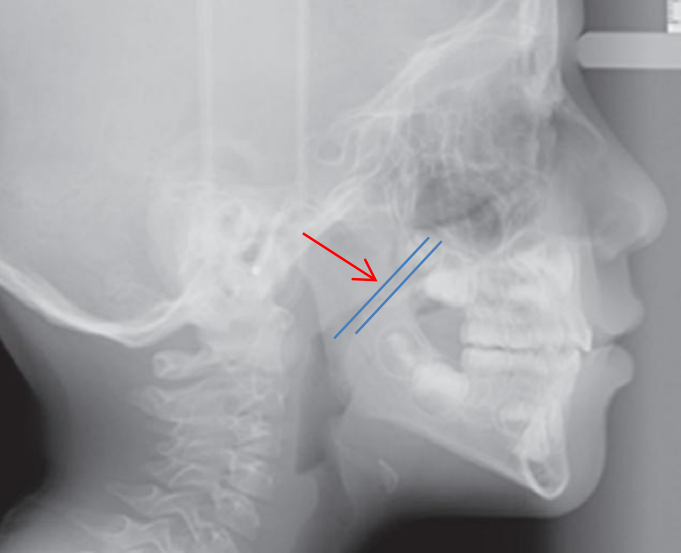

上图即为鼻咽侧位片,图中所见腺样体明显肥大,鼻咽气道明显受压狭窄.

主要用于诊断儿童的腺体肥大,以及成年人的鼻咽部占位等疾病情况

儿童腺样体肥大影像表现及诊断标准

医生看到鼻咽部侧位影片时,一开始判断 a/n 比值为 0.